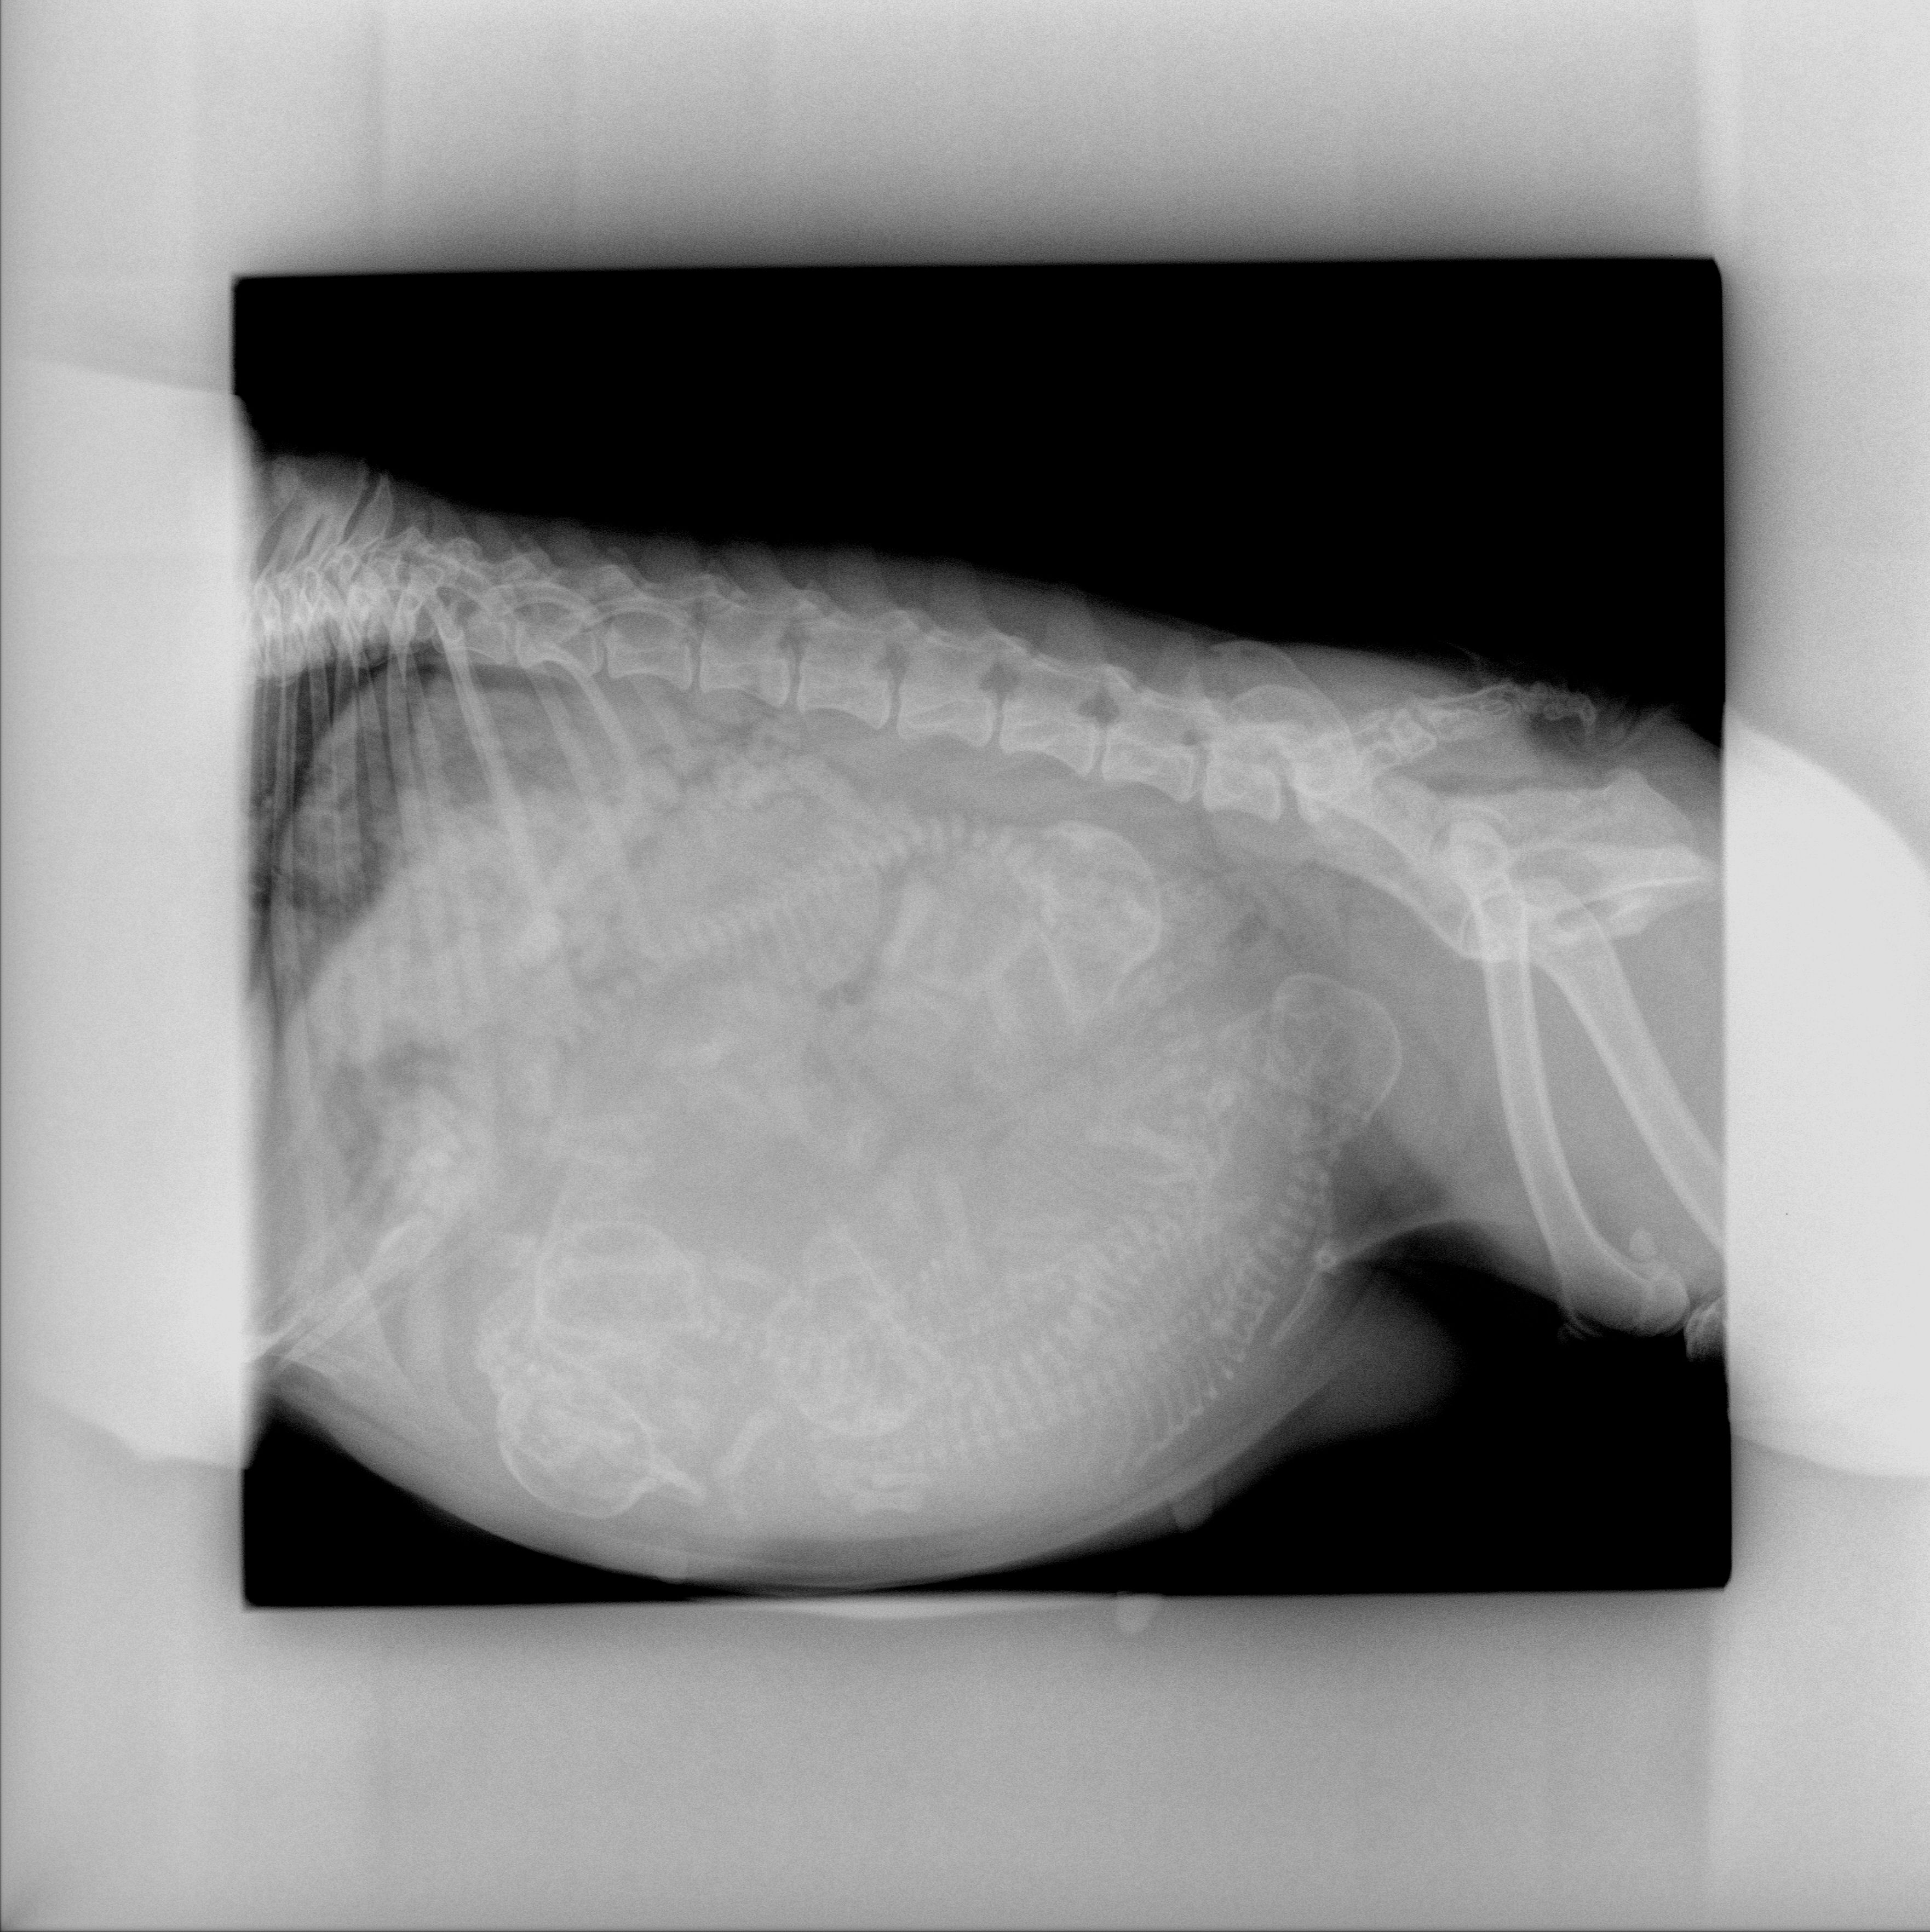

Une radiographie, après 45 jours de gestation (moment où a lieu l’ossification du squelette des chiots), pourra être programmée afin de compter plus surement et définitivement les chiots.